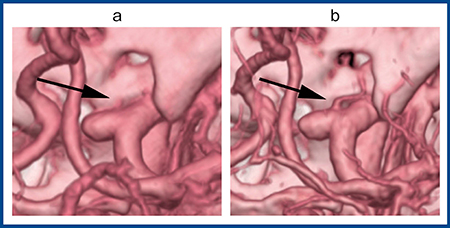

図3は内頸動脈の眼動脈瘤の症例で,手術シミュレーションを目的に,ADCT(a)とAquilion Precision(b)で同じ条件による3D VR画像を作成した。右内頸動脈から内側に動脈瘤があり,前方から細い眼動脈が分岐しているが,ADCTの3D画像にはない細い眼動脈がAquilion Precisionではしっかりと描出され,動脈瘤との位置関係が把握できる(図3 b→)。実際に手術を行う脳神経外科医にとっても,3D画像で細かい血管まで把握した上で手技に当たれるメリットは大きいと考えられる。

図3 内頸動脈眼動脈瘤の3D再構成画像

a:ADCT b:Aquilion Precision